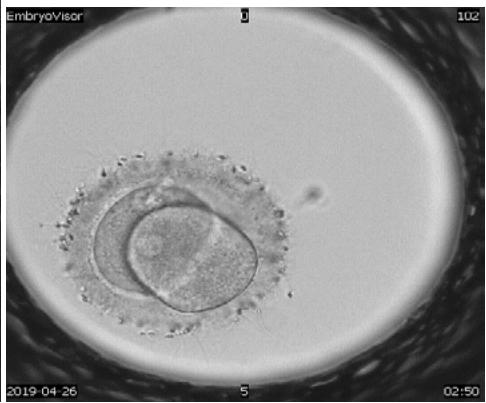

The embryological stage of ART programs is one of the most important, since the assessment of the quality of oocytes, their fertilization and in vitro cultivation to the stage of preimplantation embryos largely determines its success. Morphological evaluation of embryos is the main method of embryo selection. Time-lapse microscopy is one of the modern methods of selecting a high-quality embryo for transfer. In the analysis of many retrospective and prospective studies, they emphasize the advantage and lack of differences compared to traditional morphological assessment of the quality of embryos Almost all publications devoted to timelapse microscopy have focused on determining the timing of specific events of embryo division and then using this information to create algorithms that help to select embryo for transfer.

A detailed view of techniques used to assess human embryo development to enhance reproductive potential.